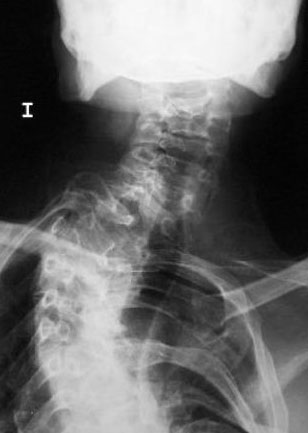

Artrosis cervical.